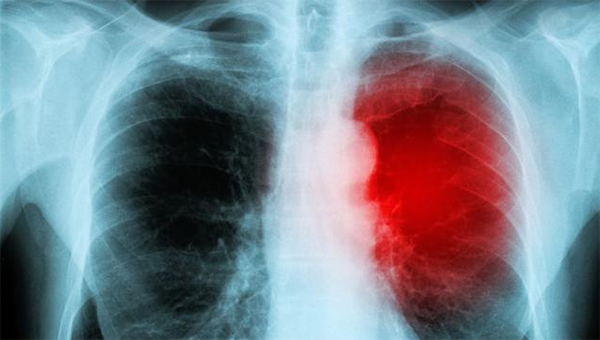

肺部CT多久做一次合适

做CT的频率要根据你检查的目的而定,是体检?肺炎治疗后复查?肺结节复查?还是肿瘤术后复查?病情不同,检查的频率不同。